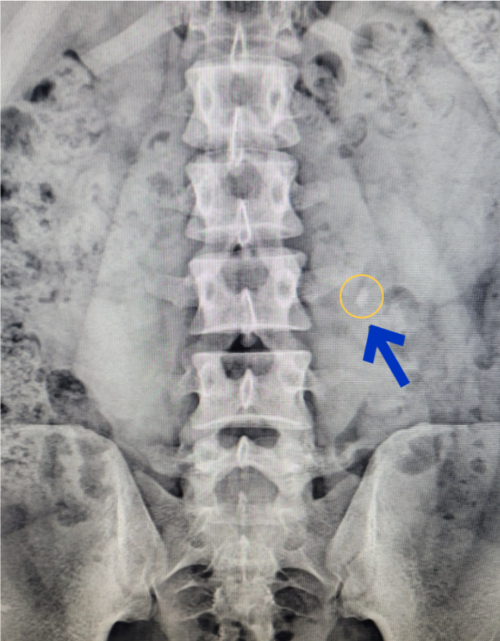

신장요관방광 단순촬영 ( KUB )

- xray 촬영으로 현재의 상태 확인.

KUB 위와 같은 방법으로 요로결석을 진단 후 치료를 하게 됩니다.